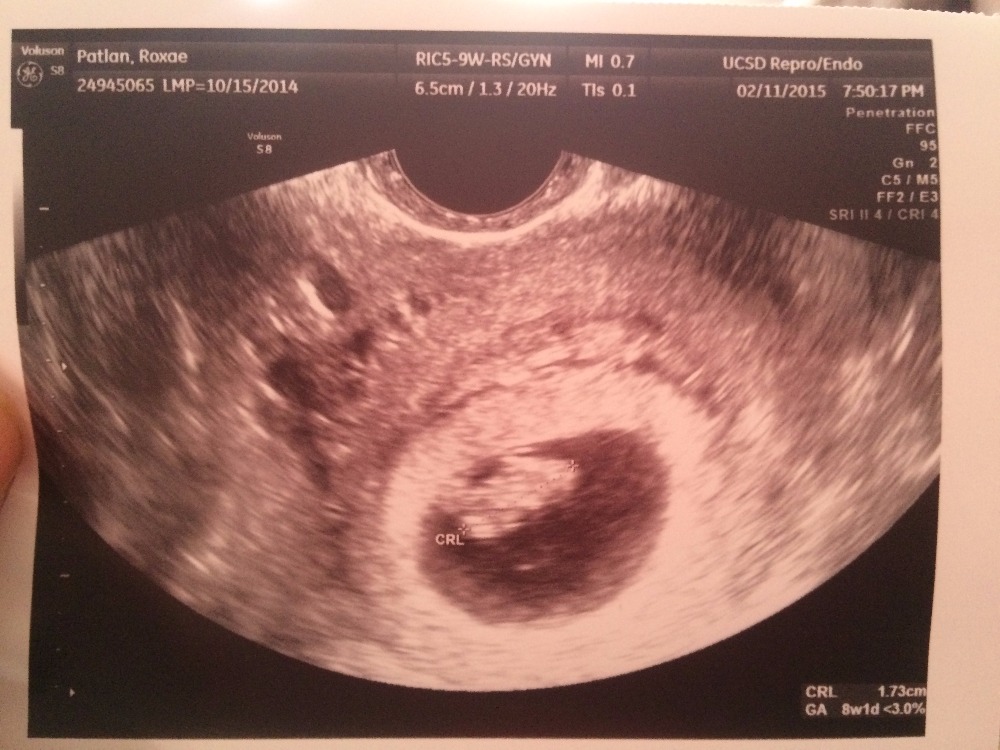

Our story begins this past Spring. We were preparing for our move to CJ's new duty station in Japan. We had just foud out we were pregnant with our fourth and were so excited for this move.

Me and the kiddos got in a car with my parents and drove for three days back to Houston where I could get the help I needed while CJ was away. That's three kiddos all 4 years and under and a VERY pregnant lady! God bless my parents for putting up with us! haha Shortly after we had arrived (like not even two weeks) I had our son, Raphael. CJ was able to FaceTime us and was able to see his baby being born! What a blessing technology can be!